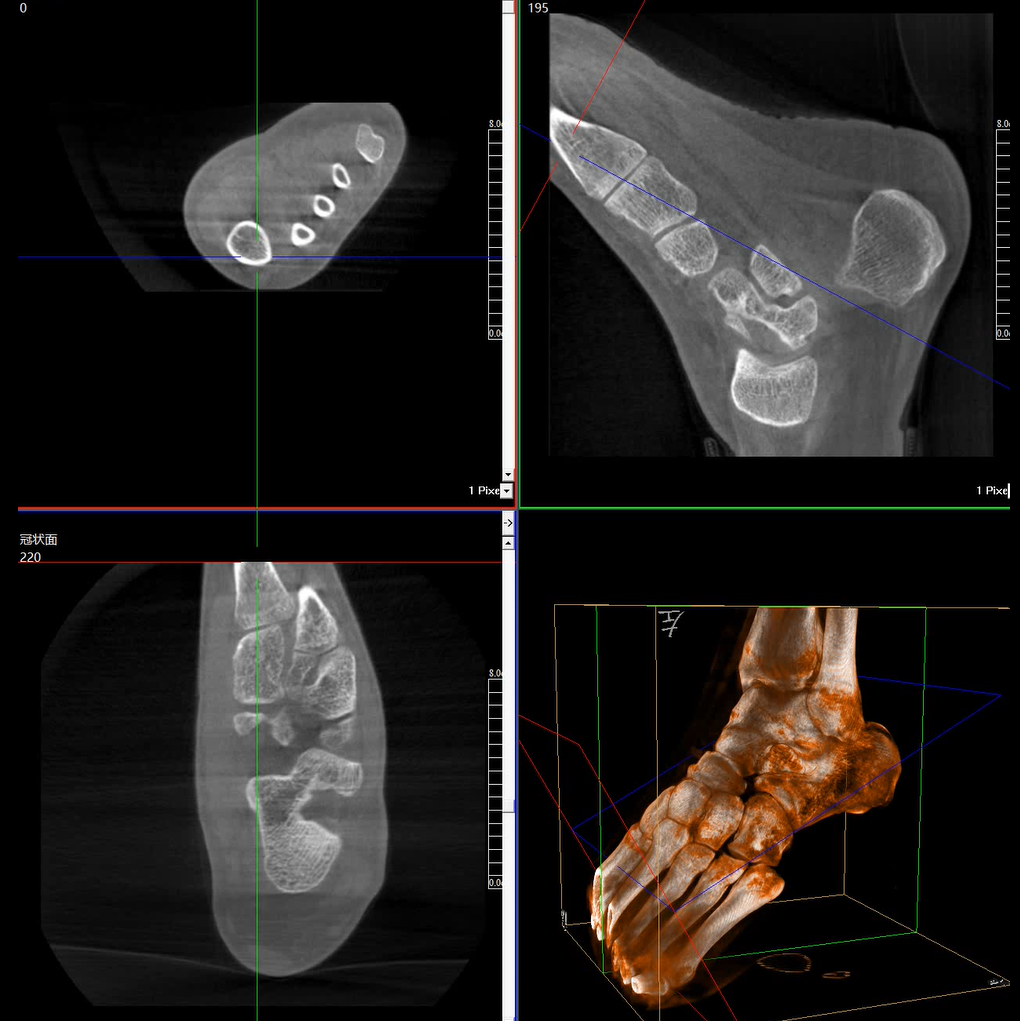

術(shù)中三維成像和橫斷面圖像提供多角度的手術(shù)診斷信息,輔助醫(yī)生進(jìn)行術(shù)中評(píng)估判斷,諸如骨折復(fù)位情況和內(nèi)植入螺釘?shù)某叽绾臀恢茫o助手術(shù)更好地完成。